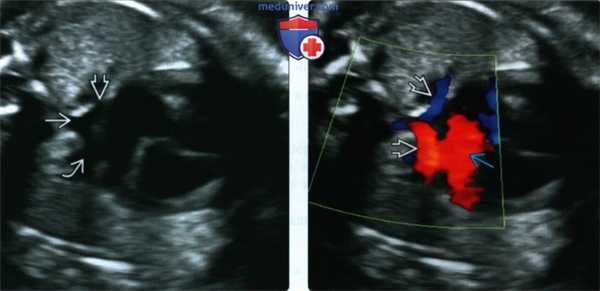

(Слева) ЭхоКГ, четырехкамерный срез. Позади предсердия определяется сосудистое образование, в которое впадают правые и левые легочные вены. ТАДЛВ в данном случае осуществляется через вертикальную вену, впадающую в плечеголовной ствол. Данная форма ТАДЛВ встречается наиболее часто.

(Справа) То же изображение в режиме ЦДК. Позади предсердия в легочных венах определяется кровоток, поступающий в общую вену.